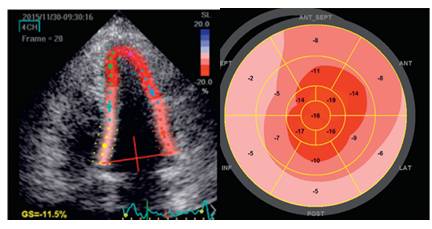

斑点追踪技术 Speckle tracking

◆心尖纵向收缩接近正常,心底部纵向收缩最差

◆牛眼征